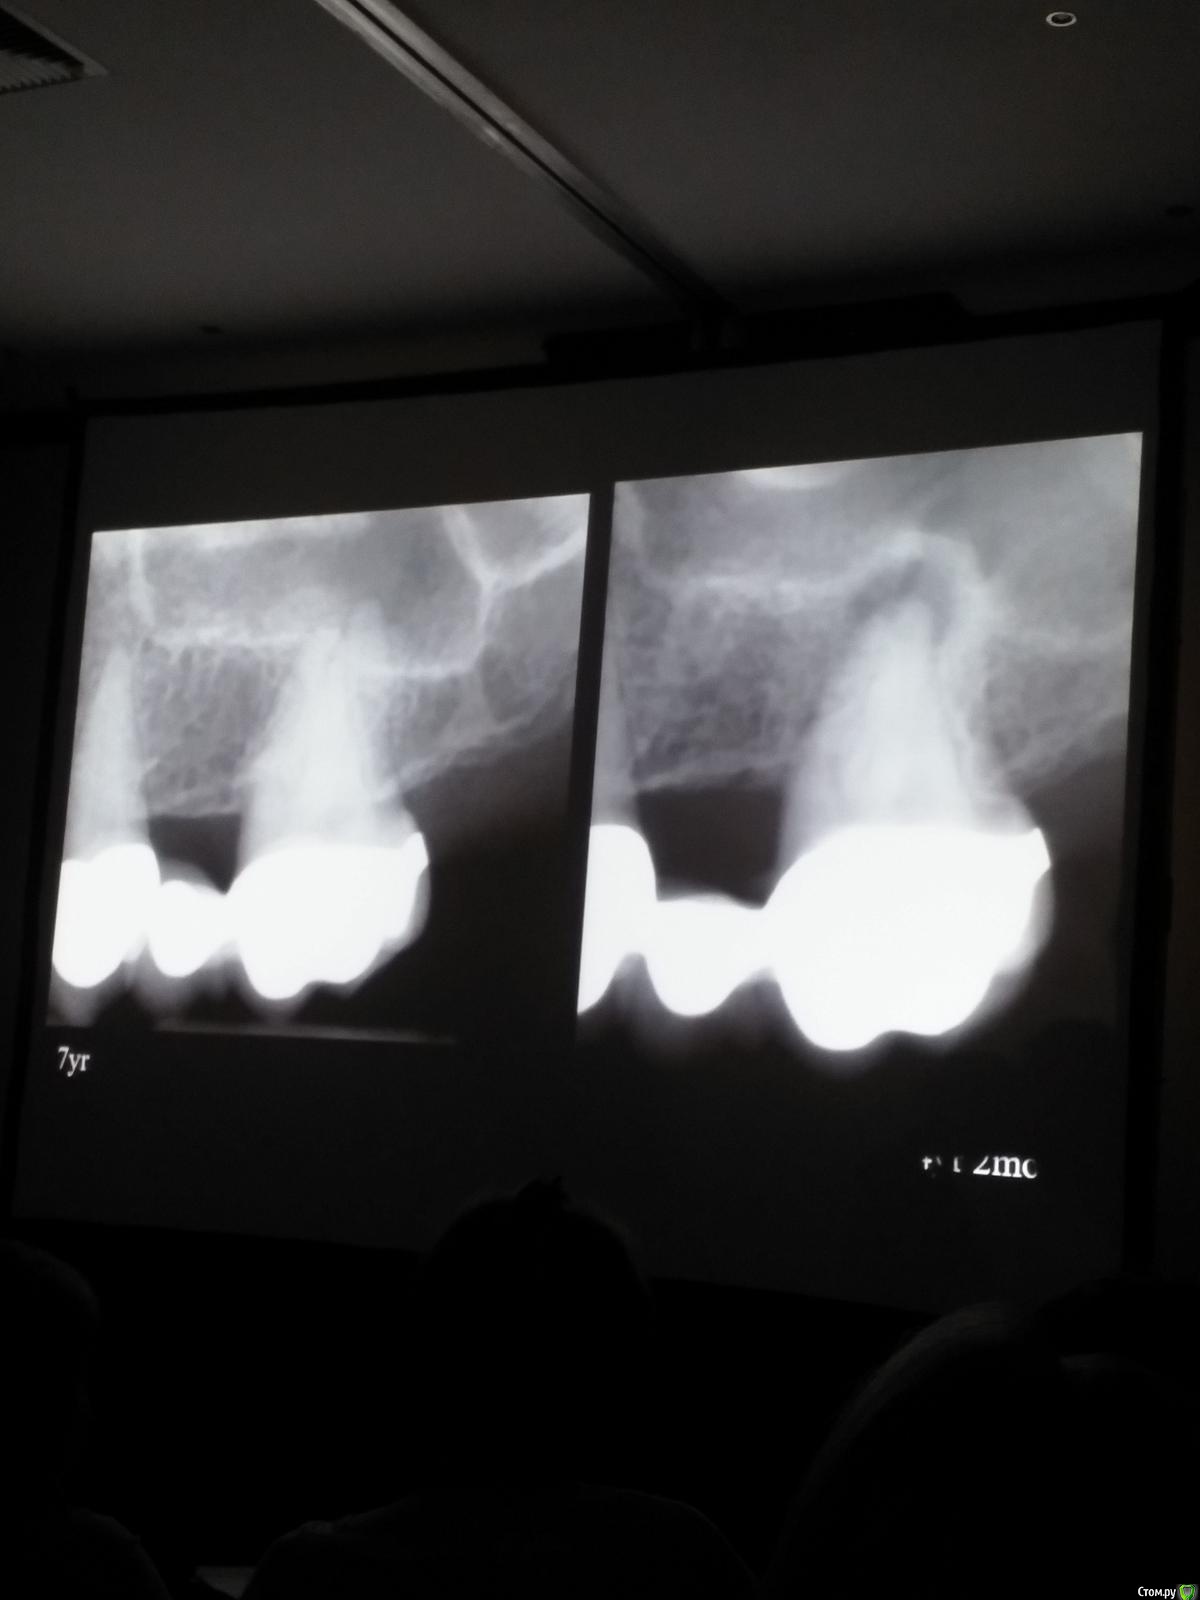

Популярный пост Kolchanov Опубликовано 11 марта, 2017 Популярный пост Поделиться Опубликовано 11 марта, 2017 (изменено) Товарищи, скажу я вам...........Вкратце. Может я где-то что-то и приврал, надеюсь, кто еще был, поправят. Честно говоря немного прибалдел от уровня Доктора. Очень, очень высоко! Приедет еще раз, пойду еще. 1) Фиссуры зондирует острым зондом и выпиливает все дотла. По факту у него уже пломбы, а не герметизация.2) Bite-wing у первичных пациентов всегда.3) Если кариес диагносцирован, то лечить его, пофиг какой он там. Эмали, дентина…4) Препарирует до твердого (или до вскрытия J ). CAD, СID… в топку. Кариес маркером не пользуется, проверяет острым зондом/экскаватором. Вычищает все дотла. Считает, что даже небольшое количество бактерий в дентине под пломбой вызывают хроническое воспаление в пульпе. С его слов у него на контроле где-то 500 вскрытий, не удивительно при таком подходе к очистке.5) Тщательная изоляция. Коффер порвался – меняет. Большое значение герметичности реставрации. под замену6) Критерии обратимости и необратимости.Гистологически, обратимый тот, что без абсцессов в пульпе, но клинически это понять нельзя, только предположить.Здесь был бы обратимый, если бы не удалил. Нет микробов в пульпе. Линия - граница обработки.Покрытие 27 лет назад. Dycal, СИЦ, композит. От дайкала одно воспоминание.7) Вскрылись. Размер перфорации, возраст и прочее не играют роли, важно только состояние пульпы, т.е. диагноз.Примеры перфораций.8) Кровотечение останавливает стерильным ватным шариком. Если останавливается, то покрытие, если нет, то пульпотомия или пульпэктомия.9) Использует гидроокись кальция (порошок), перекрывает Dycal или СИЦ. Потом восстановление Нередко под IRM, потом все убирает (через пару-тройку месяцев) и смотрит, что получилось. Порой приходится повторять! Использует и МТА, его тоже убирает.10) Наблюдение 6мес, 1 год, 2…. Все может провалиться и через месяц и через 24 года.Примеры проваловНиже - 24 года спустя появилась дуля. 11) Неравномерная облитерация полости зуба на RG (после покрытия) – признак текущего хронического воспаления, где-то остались микробы. Рекомендует эндо.12) Мостик который образуется – это не дентин! И одонтобласты не регенерируют и новые не образуются. Что это такое он и сам не знает, но раз это твердые ткани, то и наплевать.Вот фиолетовое это дентинные опилки вмурованные в розовую ткань бог знает кем сформированную.13) Пульпотомия в зубах с несформированной верхушкой и в сформированных, при подозрении на частичное поражение коронковой пульпы. Иссекается стерильным алмазным бором часть пульпы, гидроокись, временная пломба на 90 дней, после повторное раскрытие, оценка результата, восстановление в случае формирования твердых тканей. Гипохлоритом можно мыть, можно не мыть, если мыть, то 0,5-1%.14) В апикальной части пульпа чаще витальна, чем нет.15) Периапикальные поражения возникают по причине поступления токсинов микробов с током крови, а не самих бактерий.16) За апикальные расширения в полностью некротических случаях. Надо механически отодрать биопленку и срезать инфицированный дентин. На ирриганты надежды мало.17) Биопленка на поверхности в 6% случаев.Синенькие пид@расы18) Обработку проводить нежно, краун-даун. Чередовать с H-файлом, чтобы посмотреть докуда распространяется некроз.19) Патенси в витальных кейсах не колоть, сохранять витальную пульпу в констрикции!Формирование еще большего сужения в констрикции за счет сохранения витальной пульпы. Изменено 11 марта, 2017 пользователем Kolchanov 31 Ссылка на комментарий

Популярный пост Kolchanov Опубликовано 12 марта, 2017 Автор Популярный пост Поделиться Опубликовано 12 марта, 2017 Второй день.1) Дезинфекция зуба и раббер дама перед работой. Вначале установка системы, потом протирка тампоном 30% перекиси, потом протирка всего йодинолом. Потом преп, потом повторение и только потом доступ к к/к. Все старые реставрации надо убрать, кариес убрать, противник лечения через коронку.2) Гидроокись на неделю. Замешивает на стерильном физрастворе. При необходимости повторяет. Т.е. в случае сохранения свища, симптоматики, экссудации, запаха. Если свищ не исчезает после трех смен временных вложений, то хирургия.3) Пломбирует латеральной компакцией. Лучше контроль длины обтурации.4) Высушивание канала стерильными штифтами, на рабочую длину минус 1мм. После высушивания штифт оставляется на 60с. в канале и должен выйти сухим.5) Определение рабочей длины. Витальные случаи. АЛ должен три раза дать одну и ту же картинку в определенной точке + проверка RG. Девитальные случаи. На АЛ полагаться сложно, т.к. из-за наличия резорбции констрикции может врать, больше ориентируется на RG.6) Использует ЦОЭ силеры. Резорбируются при незначительном выведении. Резорбируются в канале, позволяя закрыть апекс цементоподобной тканью. Вот так вот.Случаи исчезновения силера, как за пределами канала так и в канале7) Выведение материала (не важно какого) в большом объеме способно вызвать защитную реакцию тканей. Которая должна пройти спустя некоторое время. (иногда это будет 25 лет J Случай 1ый. Студенты наломали инструментов. Периодонтит на RG через год. Резекция и гистология. Бактерий не обнаружил. Да, маленькое замечание. Каждый препарат дает 500-600 срезов. И ищет он на всех. Объем работы, конечно….Случай 2й. Его собственный. Периапикальное поражение, обнаруженное на реколле через 10 лет зажило еще через 15.8) «Функционирующий зуб» считает результатом неприемлемым. Осталась инфекция с которой надо что-то делать. То, что бактерий можно замуровать в дентинных трубочках и под пломбировочным материалом, считает неправильным. Продукты метаболизма один фиг будут просачиваться и могут поддерживать реакцию воспалительную.Случай. Синее – маленькая кучка микробов, предположительно, препятствовавших заживлению очага.9) Биопленка на поверхности корня может принимать вид кальцификатов (камней) и тут уже только хирургия в помощь. При длительном существовании свищевого хода, например.Черное - это камни вокруг апикального отверстия. И гистология их с кучей синих микробов.Здесь камни на фуркации и отсутствие заживления и свищ даже после ретроградной обработки и пломбировки.А здесь вообще чертова уйма камней. И зацените разветвление канала в этом боковом резце (последнее фото препарата). 10) Реваскуляризация.В некротических случаях дентина не образуется, т.к. одонтобластов нет и не будет новых. Образуется та самая бог знает какая ткань, которая даже и с корнем не связана может быть. Суть здоровый дентикль-петрификат. А в витальных это не реваскуляризация, а обычное формирование корня. Так что нечего тут.11) Трещины дентина.Советует расшивать, братья и сестры. Без фанатизма, если нет симптоматики, но, по возможности максимально. Если есть симптоматика, то там уже по обстоятельствам. Чертова уйма микробов там и ползет, ползет к пульпе. Надеюсь, что еще раз этот замечательный Доктор приедет. Схожу с удовольствием. 2 23 Ссылка на комментарий